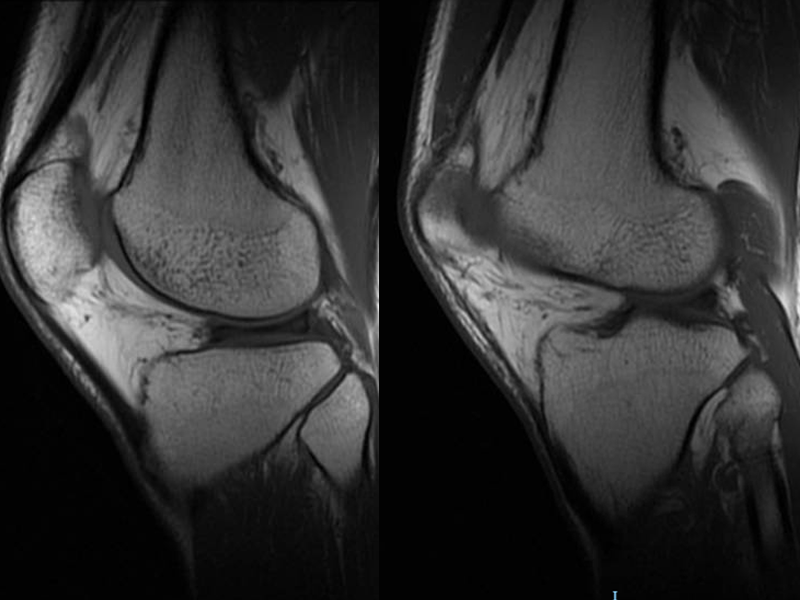

患者未行特殊处理,症状无明显改善,遂到我院就诊,对其进行左膝关节检查,无明显肿胀,外侧间隙压痛,浮髌试验。行左膝关节磁共振检查提示左膝半月板撕裂,予以消炎镇痛治疗后无明显缓解。今为进一步手术治疗,门诊拟“左膝半月板损伤”收入我科。患者自发病以来,精神、胃纳、睡眠可,大小便如常,近期体重无明显变化。

左侧膝关节,对比外侧半月板前角磨损,后角及体部撕裂伤;前交叉韧带及内侧副韧带挫伤较前改善;髌骨挫伤,大致同前;髌骨囊及关节囊少量积液,积液较前吸收;腓肠肌内侧头及周围肌间隙水肿较前吸收改善。